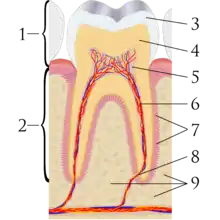

A tooth is composed of an outer shell of calcified hard tissues (from hardest to softest: enamel, dentin, and cementum), and an inner soft tissue core (the pulp system), which contains nerves and blood vessels. The visible parts of the teeth in the mouth – the crowns (covered by enamel) – are anchored into the bone by the roots (covered by cementum). Underneath the cementum and enamel layers, dentin forms the bulk of the tooth and surrounds the pulp system. The part of the pulp inside the crown is the pulp chamber, and the central soft tissue nutrient canals within each root are root canals, exiting through one or more holes at the root end (apical foramen/foramina). The periodontal ligament connects the roots to the bony socket. The gingiva covers the alveolar processes, the tooth-bearing arches of the jaws.[42]: 1–5

Enamel is not a vital tissue, as it lacks blood vessels, nerves, and living cells.[18] Consequently, pathologic processes involving only enamel, such as shallow cavities or cracks, tend to be painless.[18] Dentin contains many microscopic tubes containing fluid and the processes of odontoblast cells, which communicate with the pulp. Mechanical, osmotic, or other stimuli cause movement of this fluid, triggering nerves in the pulp (the "hydrodynamic theory" of pulp sensitivity).[19] Due to the close relationship between dentin and pulp, they are frequently considered together as the dentin-pulp complex.[43]: 118